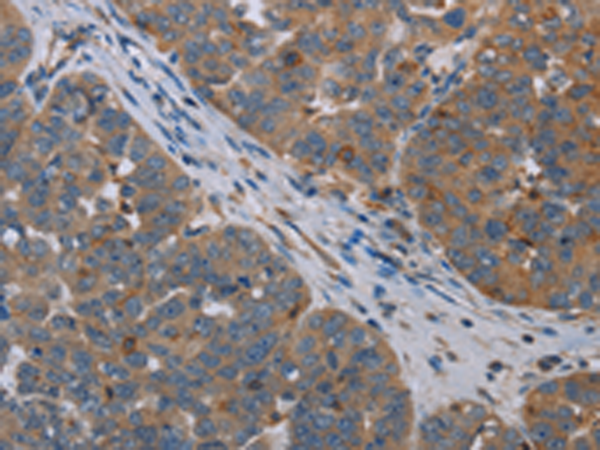

分类: 科研抗体货号: P04997别名: IK1; SK4; KCA4; hSK4; IKCA1; hKCa4; KCa3.1; hIKCa1应用: IHC反应种属: Human

分类: 科研抗体货号: P05123别名: FDP; MIAL1应用: IHC反应种属: Human, Mouse